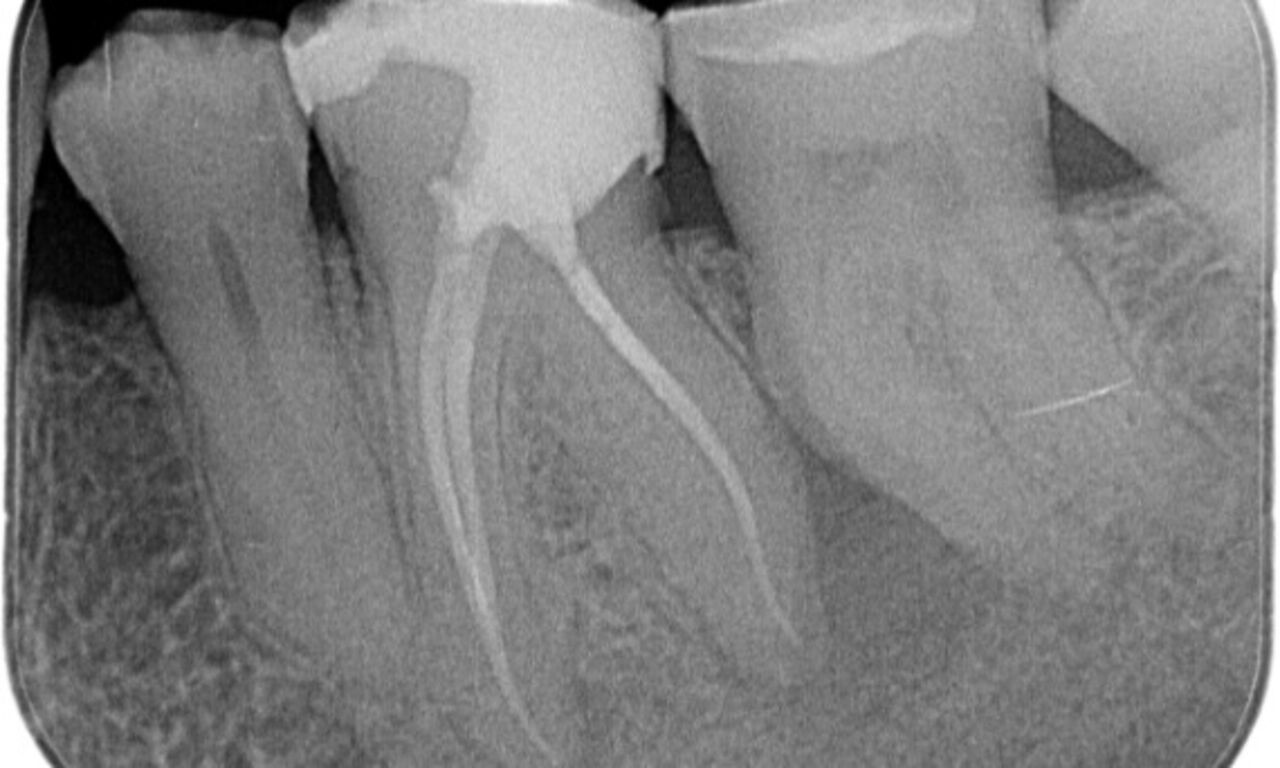

Periapical radiolucency associated primarily with the distal root and loss of lamina dura on the mesial root.

TruNatomy was chosen in this case to allow a caries leveraged approach and a focus on pericervical dentin preservation especially on the mesial aspect where the tooth had a more minimal restoration.

"A patient and process centered success."

Dr. Cowie